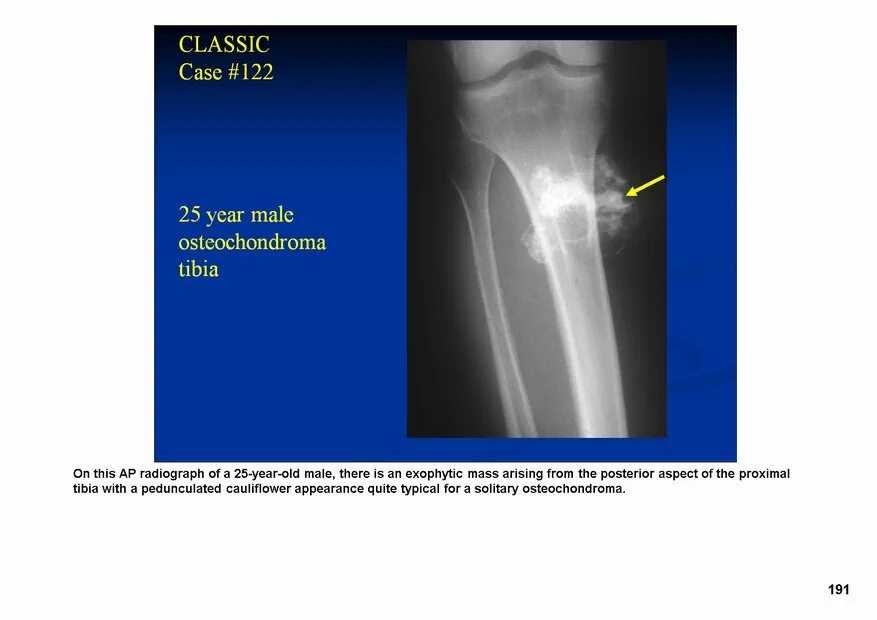

Экзостоз мкб 10